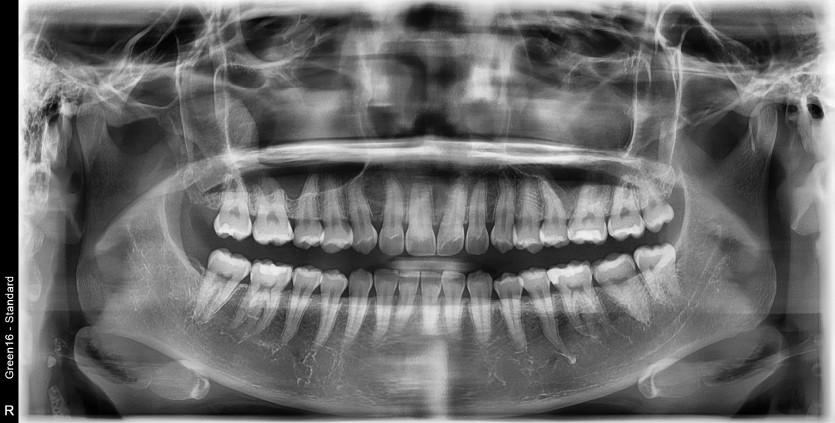

#28,38 사랑니 발치

구강 외과 전문의가 당일 발치했습니다.